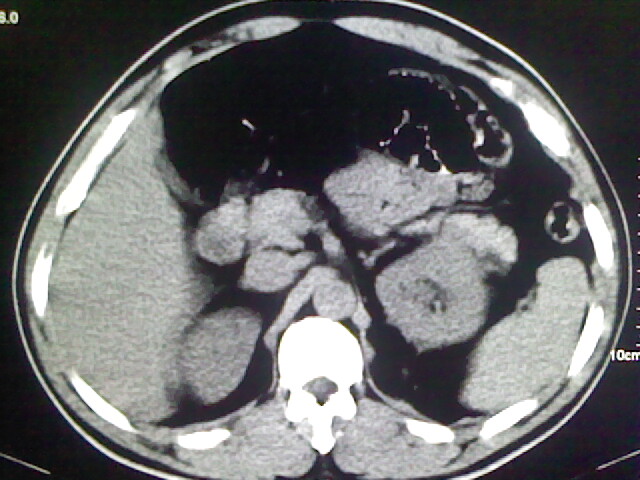

以下是引用zsl6918在2009-2-7 7:29:00的发言:[br]请提供介入的方式方法,肾及输尿管改变考虑与介入损伤有关,漏了,尿液外渗。

以下是引用余辉在2009-2-7 8:27:00的发言:[br]可能是硬化剂烧穿囊壁进入肾盂输尿管了,尿漏。不除外介入或碎石术后合并感染[br]患者术后怀疑结石,接着就碎石了?就怀疑没有确诊吗?碎石用的什么方法?气压弹道还是体外超声?如果这样的话责任人都难找

以下是引用随光逐影在2009-2-7 8:46:00的发言:[br]支持3楼意见。[br]另:不排除左肾及肾周感染可能。